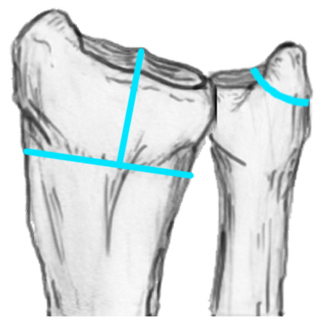

Distal Radius Angles

- radial volar tilt 11°

- radial inclination 22°

- radius is 11 mm longer than ulna

- ulna variance 2mm positive on average